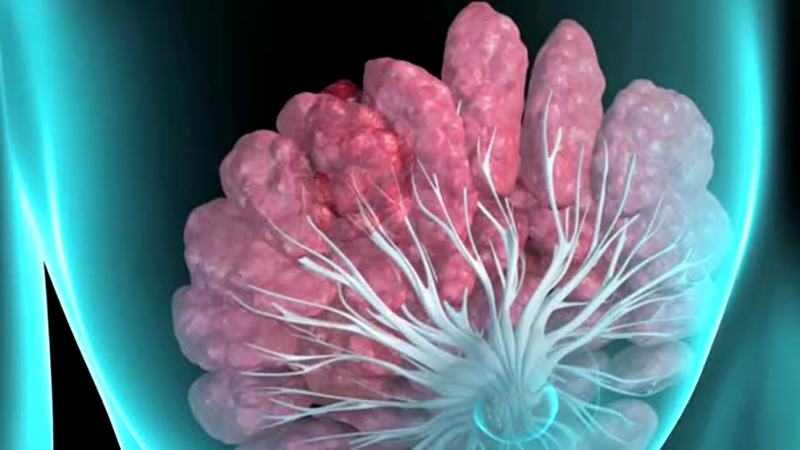

ساخت سامانه بومی برای تشخیص اولیه سرطان سینه

ICTPRESS - پژوهشگران دبیرستان انرژی اتمی تهران موفق شدند سامانهای طراحی کنند که با وارد کردن نیرویی کنترلشده و بدون ایجاد درد، خواص مکانیکی بافت سینه را برای تشخیص اولیه سرطان سینه اندازه گیری میکن